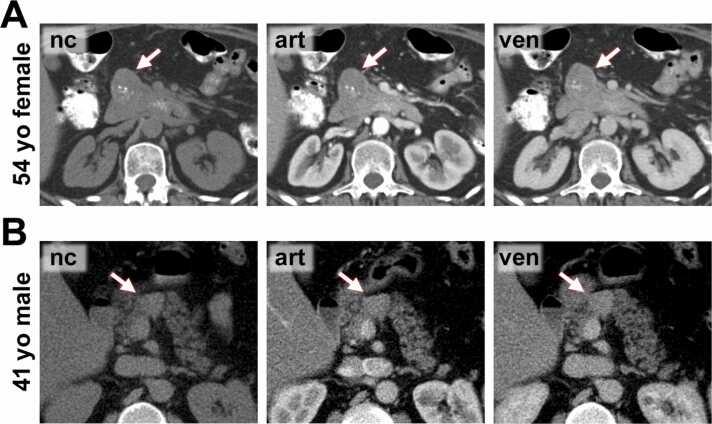

The present study aimed to compare the computed tomography (CT) and magnetic resonance imaging (MRI) features of solid pseudopapillary neoplasms (SPNs) and pancreatic neuroendocrine neoplasms (pNENs).

Lesion imaging features of 39 patients with SPNs and 127 patients with pNENs were retrospectively extracted from 104 CT and 91 MRI scans.

Compared to pNEN patients, SPN patients were significantly younger (mean age 51.8 yrs versus 32.7 yrs) and more often female (female: male ratio, 5.50:1 versus 1.19:1). Most SPNs and pNENs presented as well-defined lesions with an expansive growth pattern. SPNs more often appeared as round or ovoid lesions, compared to pNENs which showed a lobulated or irregular shape in more than half of cases (p<0.01). A surrounding capsule was detected in the majority of SPNs, but only in a minority of pNENs (<0.01). Hemorrhage occurred non-significantly more often in SPNs (p=0.09). Signal inhomogeneity in T1-fat-saturated (p<0.01) and T2-weighted imaging (p=0.046) as well as cystic degeneration (p<0.01) were more often observed in SPNs. Hyperenhancement in the arterial and portal-venous phase was more common in pNENs (p<0.01). Enlargement of locoregional lymph nodes (p<0.01) and liver metastases (p=0.03) were observed in some pNEN patients, but not in SPN patients. Multivariate logistic regression identified the presence of a capsule (p<0.01), absence of arterial hyperenhancement (p<0.01), and low patient age (p<0.01), as independent predictors for SPN.

The present study provides three key features for differentiating SPNs from pNENs extracted from a large patient cohort: presence of a capsule, absence of arterial hyperenhancement, and low patient age.

与pNEN患者相比,SPN患者明显更年轻(平均年龄51.8岁对32.7岁),且女性更为常见(女性与男性比例为5.50:1对1.19:1)。大多数SPN和pNEN表现为边界清晰的病变,呈膨胀性生长模式。与pNEN相比,SPN更常表现为圆形或椭圆形病变,而pNEN在超过一半的病例中呈分叶状或不规则形状(p<0.01)。大多数SPN可检测到周围包膜,但pNEN中只有少数有包膜(p<0.01)。SPN中出血的发生率略高,但无统计学意义(p=0.09)。在SPN中更常观察到T1脂肪饱和成像(p<0.01)和T2加权成像(p=0.046)中的信号不均匀以及囊性变(p<0.01)。pNEN在动脉期和门静脉期的强化更常见(p<0.01)。部分pNEN患者观察到局部区域淋巴结肿大(p<0.01)和肝转移(p=0.03),但SPN患者未出现。多因素逻辑回归分析确定包膜的存在(p<0.01)、无动脉期强化(p<0.01)和患者年龄较小(p<0.01)是SPN的独立预测因素。

本研究从大量患者队列中提取了区分SPN和pNEN的三个关键特征:包膜的存在、无动脉期强化和患者年龄较小。